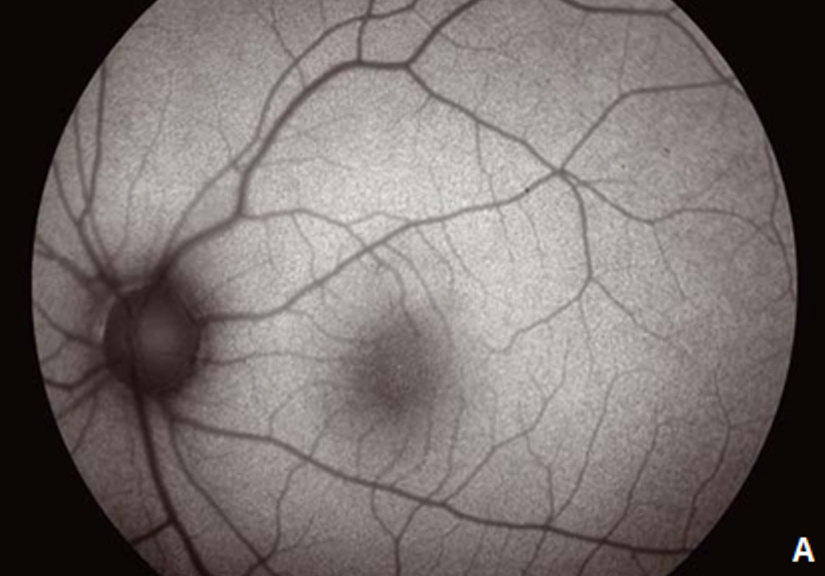

L’autofluorescence est une technique d’imagerie non invasive qui permet de mettre en évidence des dysfonctionnements de l’épithélium pigmentaire, couche cellulaire indispensable au bon fonctionnement de la rétine sus-jacente.

Elle permet de réaliser une cartographie de la distribution de la lipofuscine dans les cellules de l’épithélium pigmentaire mais aussi d’autr

es fluorophores qui peuvent s’accumuler de façon pathologique dans la rétine et l’espace sous-rétinien.